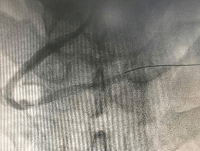

血栓抽吸前

文章图片

血栓抽吸后

当天凌晨4点 , 章叔突发胸痛 , 直到上午8点 , 疼痛难忍的他前往附近医院就诊 , 通过心电图检查发现 , ST段明显抬高 , 呈“红旗飘飘”(急性心肌梗死的常见指征) , 医院紧急联系广医五院胸痛中心会诊后 , 建议尽快进行急诊PCI术 。 PCI术 , 在患者发生急性心肌梗塞后的最短时间窗内 , 进行的冠状动脉开通再灌注治疗 , 也是所谓的“血运重建” 。

随后 , 章叔立刻通过急诊转运到广医五院进行急诊PCI术 , 手术十分顺利 , 但由于章叔就诊时间过晚 , 心肌缺血时间较久 , 心肌大面积坏死 , 导致心脏泵血功能受损、心功能下降、血压偏低 , 通过进一步利尿、扩管、改善心功能等治疗后 , 章叔达到出院体征 , 顺利出院 。